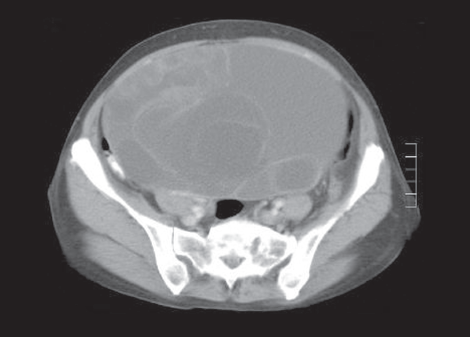

Laboratory testing. Results of a complete blood cell count, basic metabolic panel, urinalysis, amylase and lipase tests, and liver function tests were normal. A human chorionic gonadotropin urine test was negative. Abdominal and pelvic CT scans showed a large multiloculated cystic mass that arose from the pelvis and extended to the level of the diaphragm. There were multiple fibroids in the uterus and no peritoneal free fluid.

The cancer antigen 125 test (CA-125) value was 16 U/mL (normal range, less than 35 U/mL). Exploratory laparotomy revealed a large solid, cystic mass arising from the right ovary. A total abdominal hysterectomy and bilateral salpingo-oophorectomy were performed. The excised mass was 24 cm x 15 cm x 14 cm and weighed about 8 lbs; it was smooth without excrescences and was composed of gelatinous cysts. Pathological results revealed benign mucinous cystadenoma.